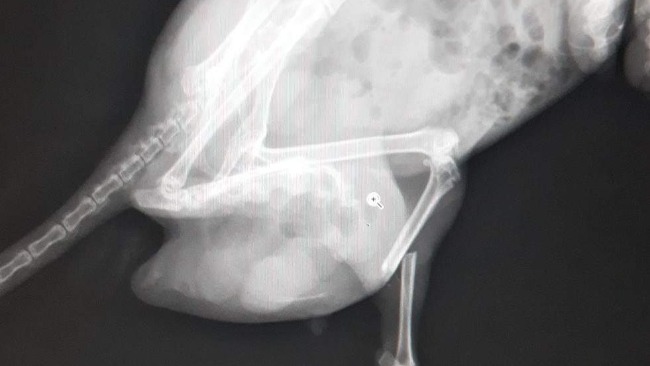

Zygmunt ze złamaną nogą i przepukliną - nie wiemy co go spotkało. Został przyciśnięty, nadepnięty? Przed nim długie leczenie - jest właśnie po operacji przepukliny i osteosyntezy.